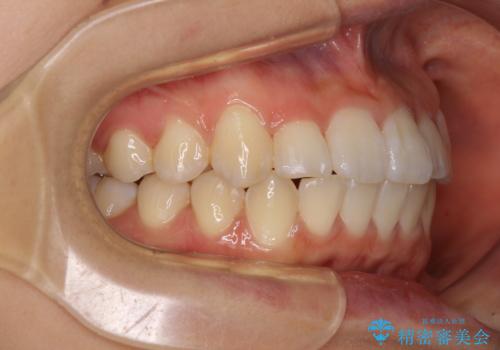

- 上下のデコボコと前歯のクロスバイトを改善したいとのことで来院された患者様です。

極力短期間で治療したいとのことで、ワイヤー装置による矯正治療を行うこととしました。

お住まいが遠方であったため、マウスピースによる矯正治療も提案しましたが、ご自身でのマウスピースの管理の面倒くささと、なるべく早く治療を終えたいとのことで、ワイヤー矯正を選択されました。